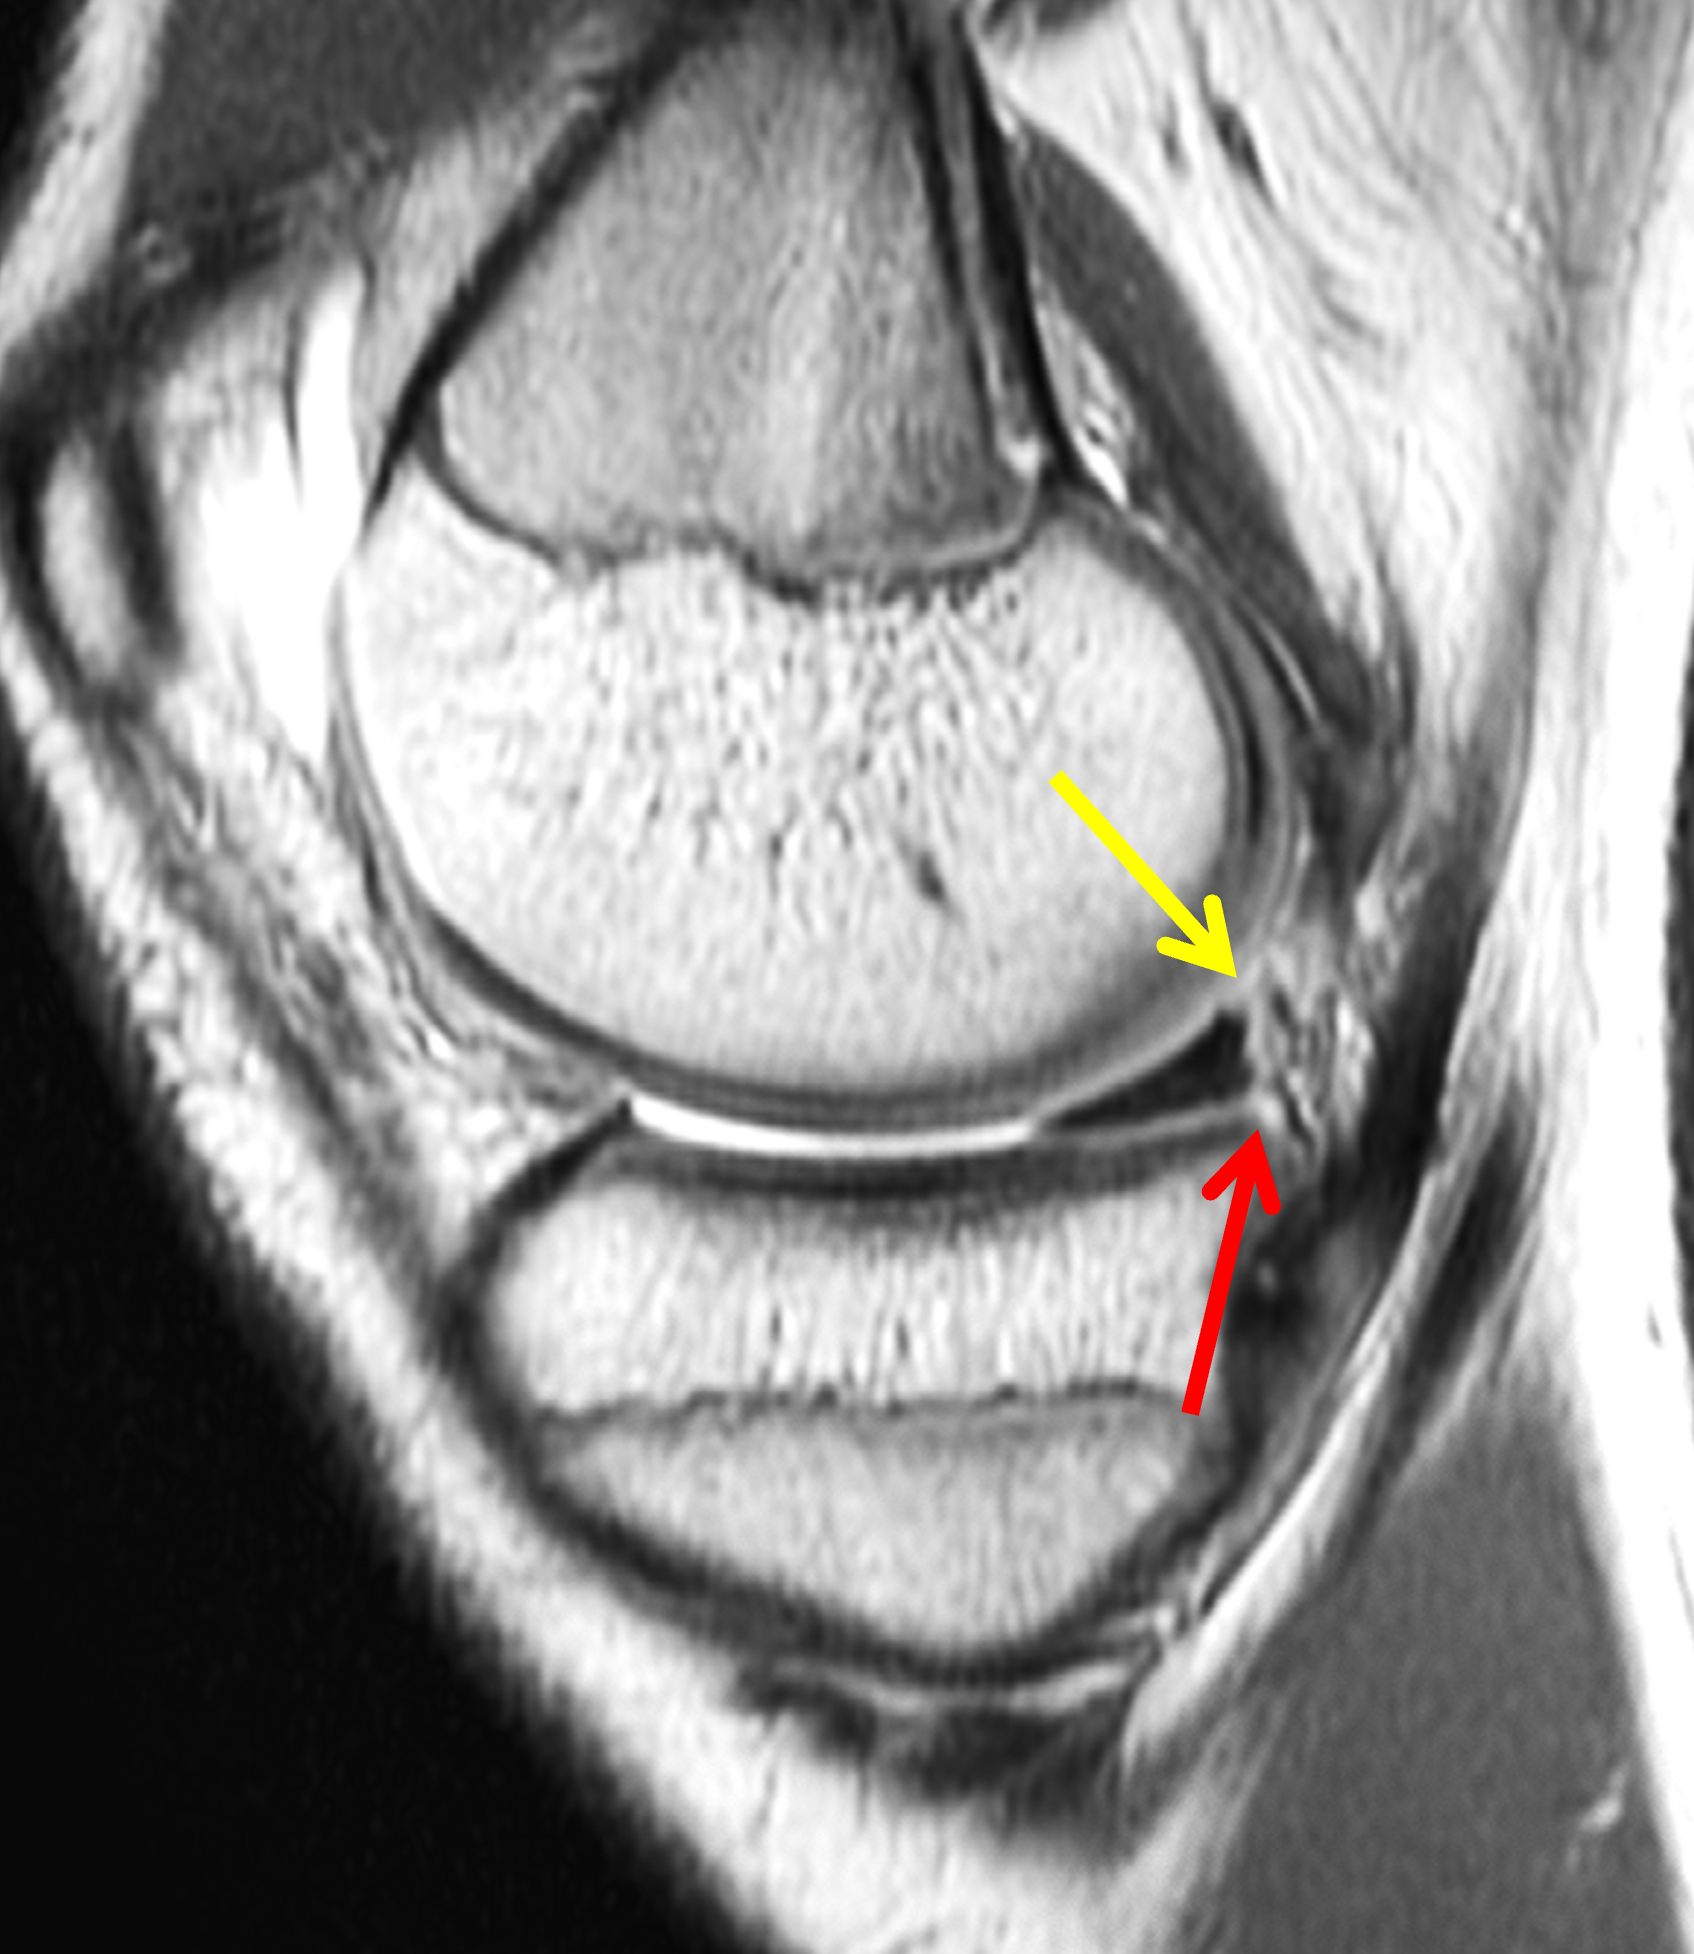

A 19-year-old collegiate baseball player sustained a twisting injury to the knee 3 weeks earlier. Sagittal (1A) proton density-weighted fat-suppressed image through the intercondylar notch, (1B and 1C) proton density-weighted images through the medial compartment, and (1D) fat-suppressed proton density image through the medial compartment are provided. What are the findings? What is your diagnosis?

Figure 2: (2A) Sagittal image through the intercondylar notch shows a complete tear of the anterior cruciate ligament (arrowheads). (2B and 2C) Near the posterior meniscocapsular junction of the medial meniscus, there is disruption of the posterior meniscotibial ligament (red arrow) and irregularity of the posterior meniscocapsular ligament (yellow arrow). (2D) On the fluid-sensitive sequence, linear high signal intensity is interposed between the ligaments and the posterior horn of the medial meniscus (arrowheads).

Anterior cruciate ligament tear with a medial meniscal ramp lesion.